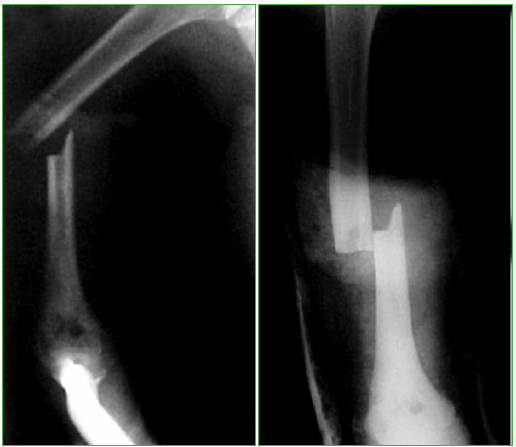

Figura 4.

Radiografía de diáfisis del húmero derecho luego de la reducción.

Figura 5.

Radiografía de diáfisis del húmero derecho consolidada.